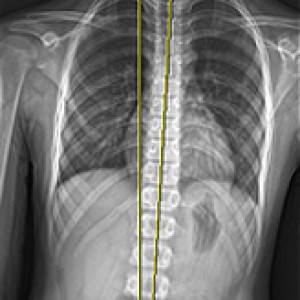

검사부터 다른 당당

“당당은 뼈만 보지 않습니다.”

근육과 근막의 정렬을 함께 진단하며, 풀 스파인 촬영을 통해 머리부터 모든 고관절, 발의 정렬까지 함께 파악하여 개개인에 맞는 전신 치료법을 설계합니다.

디테일하게 자세 패턴을 분석합니다.

7가지 패턴으로

정확한 진단을 합니다.

더 다양한 패턴을 바탕으로 분석 후 계획을 세우기 때문에, 진단과 치료의 정밀도가 다릅니다.

신체 부위별 틀어진 방향, 각도에 따라 카테고리별로 분류한 후, 그에 맞는 치료법을 실시합니다.

전신 엑스레이 검사